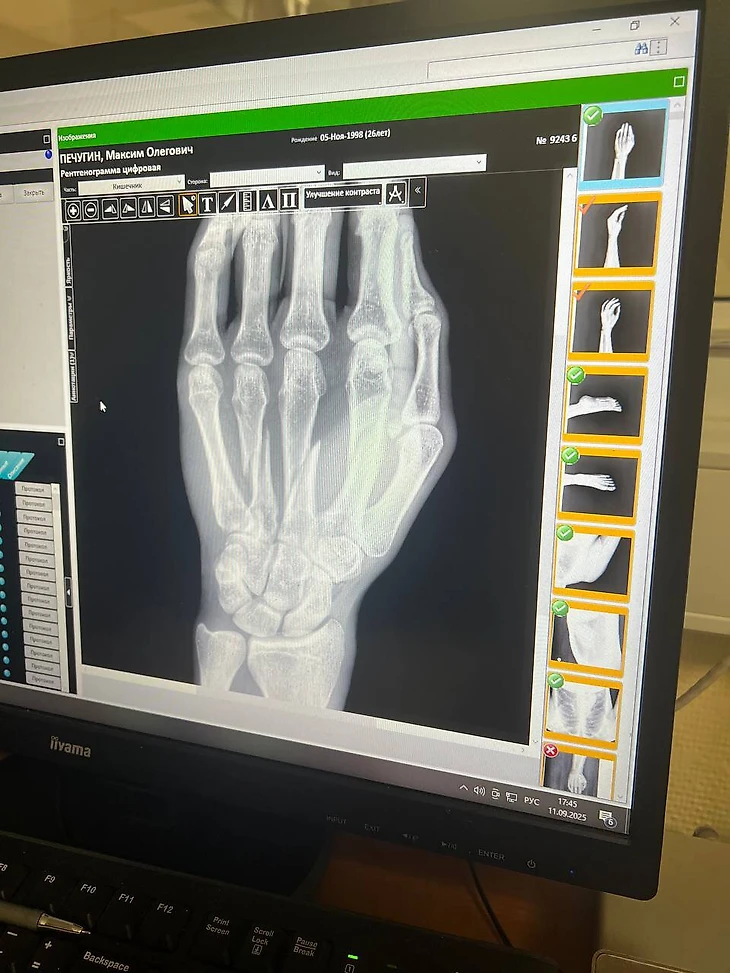

Максим Пичугин получил травму в матче FONBET Кубка России.

Форвард «Амкала» пропустил весь шестой сезон WINLINE Медиалиги из-за проблем с голеностопом, а теперь был заменен в первом тайме из-за травмы кисти.

Кадр: телеграм-канал Пичи